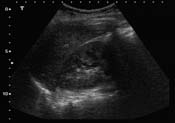

- Focussed Assessment Sonography in Trauma (FAST) Ultrasound